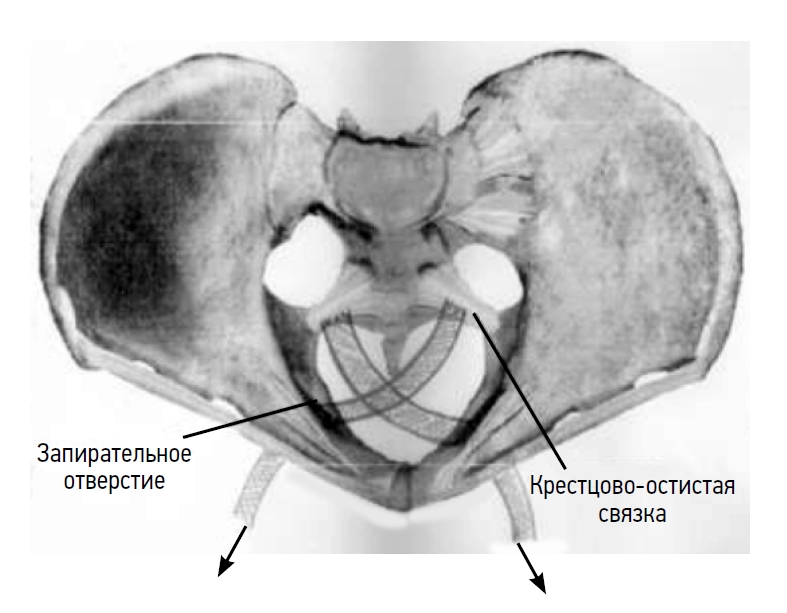

After peritonization, channels were formed toward the ischial spines and sacrospinous ligaments. Departing 1.5–2 cm from the ischial spines, a titanium fixator with a ligature was inserted into the thickness of the sacrospinous ligament. During device installation (titanium fixator), a non-absorbable fixing thread was passed through the holes in both protrusion lugs; the distal end of the bent guide was passed inside the fixator and fixed. Both ends of the thread were fixed on the handle of the guide. The conductor together with the fixator was passed into the thickness of the tissues and brought to the right sacrospinous ligament approximately 2 cm medially to the internal spine, and then it was inserted into the ligament to a depth of 1 cm. The conductor was disconnected from the fixator by rotation around its axis and removed in reverse. Pulling the ends of the ligature (ligature 1), the strength of the fixator set was checked. Similarly, the second fixator with a thread was passed and fixed in the region of the left sacrospinous ligament (ligature 2). The free ends of the threads (ligatures 1 and 2) were fixed to the sacrospinous ligaments prepared by using narrow ribbon-like mesh titanium implants alternately on both sides.

The free end of the titanium implant, fixed to the left sacrospinous ligament, was passed through the membrane and muscles of the right obturator foramen of the pelvis using a conductor under the control of the index finger, and then it was brought out into the right inguinal-femoral fold at the level of the clitoris with an incision on the skin approximately 0.7 cm (stage II). The second titanium implant was fixed to the right sacrospinous ligament and removed through the left obturator foramen.

Under visual control, the peripheral ends of titanium tape-like implants, which were brought into the region of the inguinal-femoral folds, were tightened, providing stable support for the vaginal dome. By pulling on the ends of the titanium tapes, which were brought out through the obturator membranes, the vaginal vault was fixed as high as possible in the small pelvis (stage II).

Afterward, the mesh implants were sutured with two to three slowly absorbable ligatures to the monoblock (sacral–uterine–cardinal complex), which were simultaneously sutured together (Fig.).

Fig. Fixation of mesh titanium implants to a ligamentous monoblock (sacro-utero-cardinal complex).